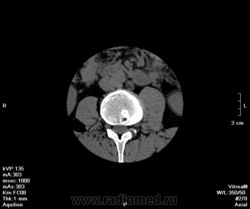

Остеопороз. Спондилодисцит (репоративная стадия?). Спондилоартроз. Деф.спондилоз. Грыжа L IV-V, распространяющаяся на правое межпозвонковое отверстие . Протрузия LV-SI.

Нейрохирурги могут думать все, что угодно. Деструкции здесь нет, явные грыжи Шморля. Натечника нет. Остепороза тоже нет, так как при остеопорозе костные балки разрежаются и остаются те, на которые ложится максимальная нагрузка, т.е. вертикальные. Картина очень напоминает гемангиомы, только более распространенные. Кроме того плотность губчатого вещества приближается к плотности мышц. Измерять позвонки в Хаунсфилдах некорректно, так как губчатая кость слишком неоднородна, кроме костных балок содержит и костный мозг и жир. Цифры будут изметь большой разброс.

Во втором случае картина совершенно нетипична для туберкулезного спондилита. Овальный очаг деструкции костной ткани с довольно четкими, ровными контурами в задних отделах тела и в дуге, не примыкающий к площадкам позвонка. Деструкции выходит на контур боковой поверхности тела, но при этом никак не отреагировали мягкие ткани. Каким образом верифицировали? То, что есть флюро архив, говорит только о поражении легких.

Что значит, за "воспаление". Воспаление как таковое часто присутствует и при остеохондрозе - т.н. "аспетический спондилит", который хорошо виден на МРТ в виде локального отека костного мозга. Речь же идет не о воспалении, а о том, есть ли деструктивный процесс вследствие остеомиелита (туберкулезной или какой-либо еще природы), или его нет. Я признаков такого процесса не вижу.

Расскажите про Шморля. Чтойто они такие. По представленным второй ряд средний скан L3-L4 задний край -вот я так себе их представляю на КТ. В L4, L5, S1 практически вся поверхность съедена, это они подряд так выстраивются? Ведь если одна, то она углублятся будет, а не по горизонтали распространяться. Может уже что другое там? Перенесенное что-нибудь?

О причинах этого можно рассуждать долго: может быть, все дело в остеопорозе, может, в нестабильности. Бог знает. Главными дифференциально-диагностическими признаками здесь служат четкость кортикального слоя и отсутствие мягкотканных изменений.